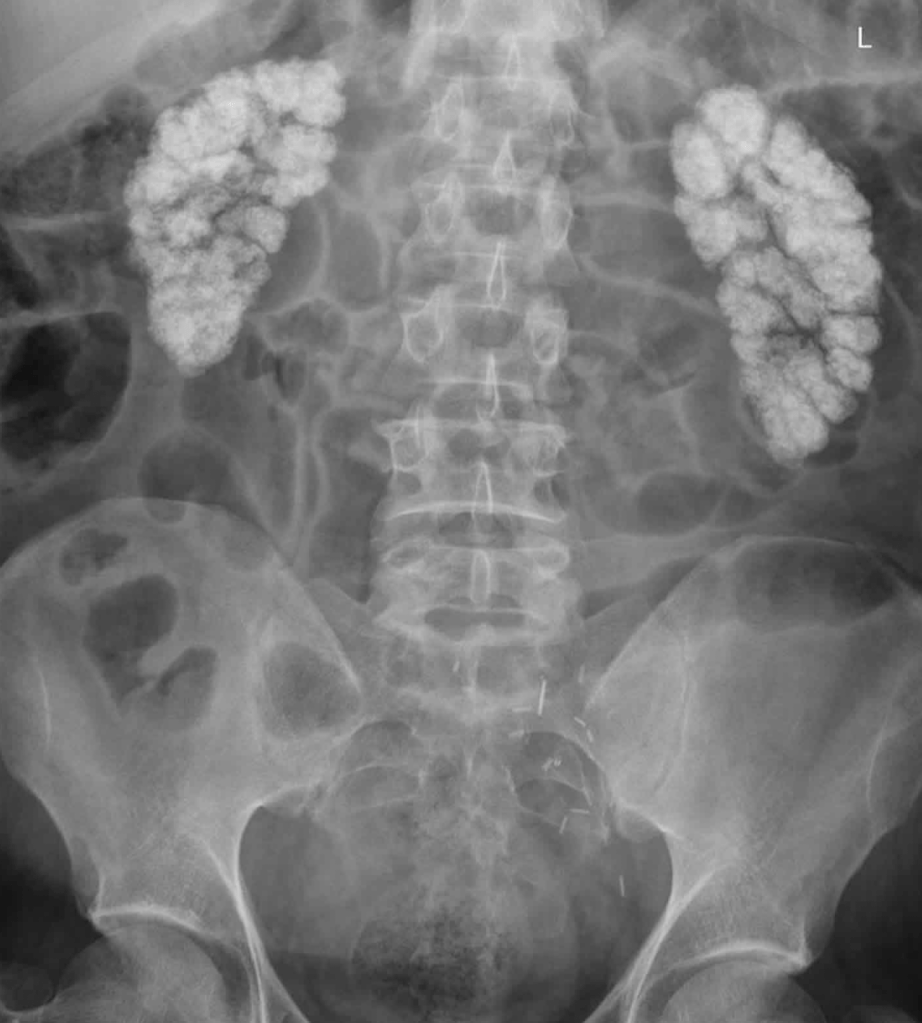

- Nephrocalcinosis:

- Which refers to renal parenchymal calcification:

- Is found in less than five percent of patients:

- Is more likely to lead to renal dysfunction